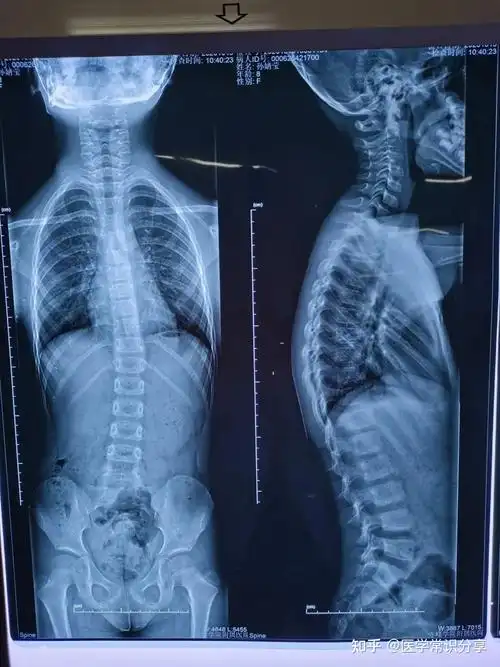

脊椎侧弯的影响与案例分享 - 知乎